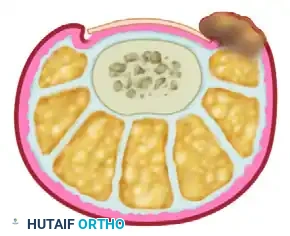

ANATOMY OF THE PERIONYCHIUM

A profound understanding of the perionychial anatomy is the cornerstone of successful surgical intervention. The nail apparatus is a complex, specialized epidermal structure designed to protect the distal phalanx, enhance tactile sensation, and regulate peripheral hemodynamics.

The perionychium comprises the following distinct anatomical entities:

* Nail Plate: The hard, keratinized structure that spans the dorsum of the distal digit. It is produced primarily by the germinal matrix.

* Nail Bed: The highly vascular soft tissue beneath the nail plate, divided into two functional zones:

* Germinal Matrix: Located proximally, extending from the proximal nail fold to the lunula. It is responsible for 90% of nail plate generation. Failure to completely ablate the germinal matrix during surgical management is the primary cause of recurrence.

* Sterile Matrix: Extends from the lunula to the hyponychium. It provides strong adherence to the nail plate and contributes minimally to its thickness.

* Nail Folds: The cutaneous structures surrounding the nail plate, including the proximal nail fold (terminating in the eponychium/cuticle) and the lateral nail folds (paronychium).

* Hyponychium: The specialized epidermal junction between the distal nail bed and the volar skin of the digit, serving as a barrier against subungual infection.

Surgical Warning: The germinal matrix extends proximally beneath the eponychium for a distance of 5 to 8 mm. Surgical or chemical matrixectomy must reach this proximal recess to ensure complete ablation of the nail-forming tissue.